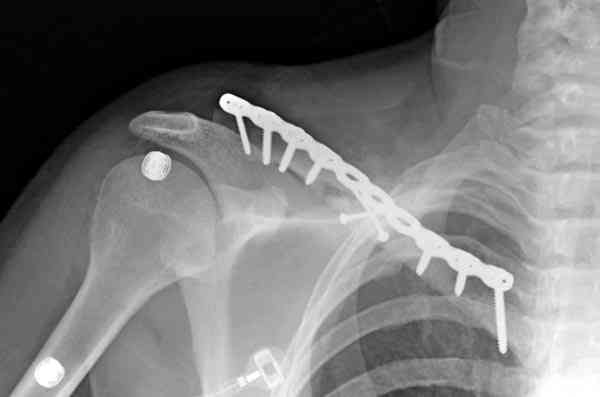

Второй случай тоже недавно оперирован по поводу

ложного сустава, в марте травма, через 4.5 половиной

операция..